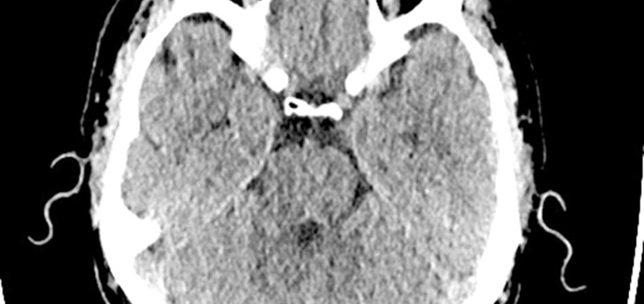

Acute macular neuroretinopathy

Sagar Jobanputra

Marcela Bohn